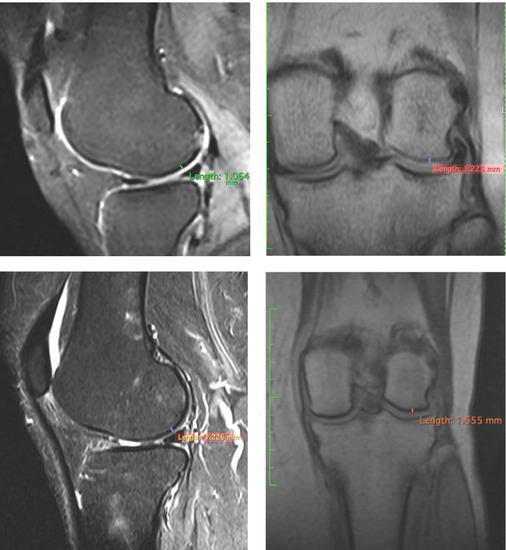

| Patients | Pre/Femoral Lateral Condyles | 3 Years/Femoral Lateral Condyles | Difference |

|---|---|---|---|

| 1 | 1.064 mm | 1.226 mm | +15.22% |

| 2 | 1.339 mm | 1.472 mm | +9.32% |

| 3 | 1.068 mm | 1.263 mm | −14.20% |

| 1 | 1.223 mm | 1.555 mm | +27.14% |

| 2 | 1.489 mm | 1.882 mm | +26.39% |

| 3 | 0.893 mm | 1.914 mm | +114.33% |